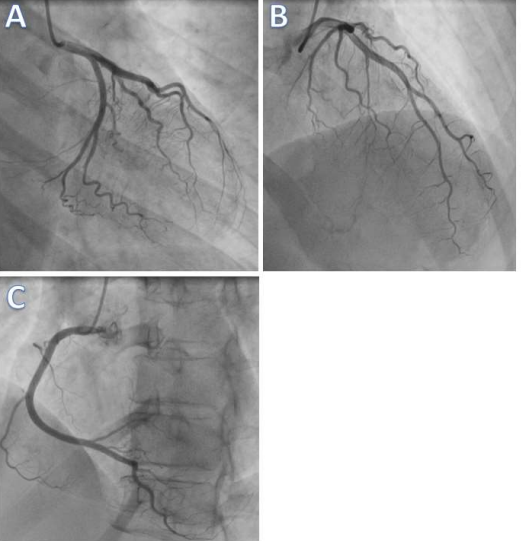

The subsequent Serum Troponin levels of the patient were done and its sharply increased to 22827 ng/mL, Immediately the patient was shifted to catheterization procedure room However, coronary angiography report shows the absence of obstructed coronary atherosclerosis or acute plaque rupture Figure 3, A B C.

Figure 3 Coronary angiography showed no significant stenosis of the coronary arteries (left coronary artery [A,B] and right coronary artery [C]).